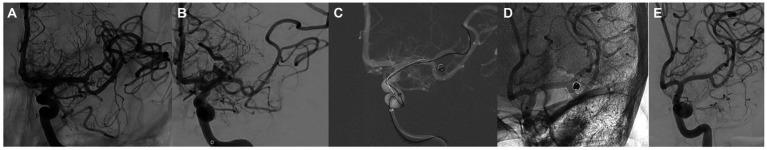

Long-term follow-up of cerebral aneurysms treated with the Silk Vista Baby (SVB) flow diverter is lacking. This study aimed to assess the technical success, procedural safety, and efficacy of the SVB (Balt, Montmorency, France) for the treatment of intracranial aneurysms in small cerebral vessels over a mid-to long-term follow-up.

We retrospectively analyzed a prospectively maintained database of patients treated with the SVB between September 2018 and June 2021. Data regarding patient demographics, aneurysm characteristics, and technical procedures were also collected. Angiographic and clinical findings were recorded during the procedure and over a period of at least 12 months.

Angiographic and clinical follow-up data were available for 50 patients/50 aneurysms. The procedural complication rate was 8%. At 12 months, the final results showed a technical success rate of 100%, the re rupture rate was 0%, neuromorbidity and mortality rates of 4 and 0%, respectively, and an almost complete occlusion rate of 94%.

缺乏对使用Silk Vista Baby(SVB)血流导向装置治疗脑动脉瘤的长期随访。本研究旨在评估SVB(法国蒙特莫朗西巴尔公司)在中长期随访中治疗小脑血管内颅内动脉瘤的技术成功率、手术安全性和疗效。

我们回顾性分析了2018年9月至2021年6月期间接受SVB治疗患者的前瞻性维护数据库。还收集了患者人口统计学、动脉瘤特征和技术操作的数据。在手术期间及至少12个月的时间内记录血管造影和临床结果。

50例患者/50个动脉瘤有血管造影和临床随访数据。手术并发症发生率为8%。在12个月时,最终结果显示技术成功率为100%,再破裂率为0%,神经功能障碍率和死亡率分别为4%和0%,几乎完全闭塞率为94%。